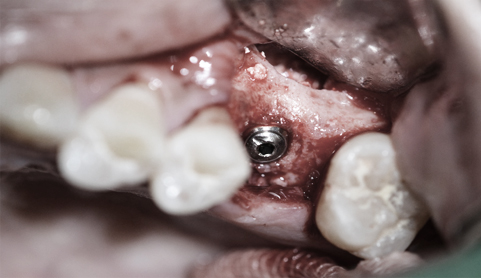

• 1차 임플란트 수술진행 Step. 02

1차 임플란트 수술 진행

임플란트 매식체를 턱뼈에 심는 과정으로 잇몸을 열고 정확한 위치에 정확한 각도로 심은 후 다시 잇몸을 덮습니다.

일반적으로 아래턱의 경우 약 3개월, 윗턱의 경우 4개월 정도 치유 기간이 소요됩니다.

• 2차 수술 진행 Step. 03

2차 수술 진행

잇몸 밖으로 기둥을 연결하여 앞으로 보철물이 장착될 수 있게 해주는 과정입니다.

임플란트의 윗부분 잇몸만을 절개합니다.

1차 수술과 준비 과정은 같지만 시간은 짧습니다.

만들어진 구조물 위에 인공치아를 만들어 끼우면 임플란트 보철 완성됩니다.